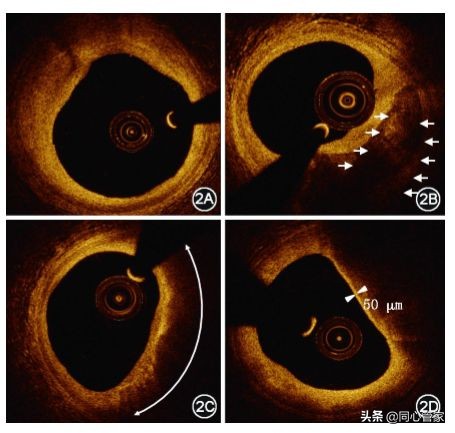

正常冠状动脉血管壁的特征是典型的3层结构,由内膜、中膜和外膜组成(如图所示)[3],内膜信号(密度)高,无病变时非常薄。但当出现病变时,OCT图像上的斑块类型可分为3类,即纤维斑块、钙化斑块和脂质斑块。

OCT“眼中”的斑块:

• 纤维斑块:强反射,均匀增生;中膜也能分得清 。

• 钙化斑块:里面密度不均一 ,外面边界很锐利。

• 脂质斑块:强衰减,信号低,边界变得不清晰(如图所示)

▲OCT检查图像斑块类型(2A:纤维斑块;2B:钙化斑块;2C:脂质斑块;2D:薄纤维帽粥样硬化斑块) [3]。